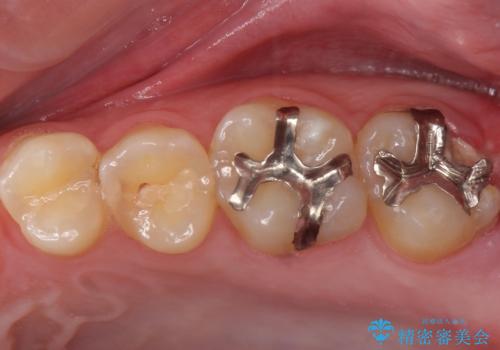

奥の虫歯 ジルコニアクラウンでの修復